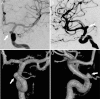

Figure 4. UIATS case recommendation resulting in the highest agreement among the internal and external reviewer cohorts

Corresponding scores in accordance with unruptured intracranial aneurysm treatment score (UIATS) features are given in parentheses. A catheter angiogram of a 47-year-old woman (3 points favoring treatment for patient age 41–60 years) who previously underwent cranial MRI for chronic headaches with (A) posterior-anterior and (B) lateral projection as well as (C) posterior-anterior and (D) lateral 3-dimensional reconstructions is shown. This incidental irregularly shaped (3 points favoring treatment for irregular morphology) anterior communicating artery aneurysm (arrow, 2 points favoring treatment for aneurysm location) had a maximum diameter of 7.6 mm (2 points favoring treatment for aneurysm diameter) with a neck diameter of 3.5 mm. Aspect and size ratios were calculated to be 2.1 and 3.8, respectively (1 point favoring treatment for aspect or size ratio greater than 1.6 or 3.0, respectively). Her medical history included arterial hypertension (2 points favoring treatment for risk factor hypertension) but no other chronic comorbidities. The resulting scoring based on the UIATS was 13 points in favor of aneurysm repair and 7 points in favor of conservative management (1 point for patient age 41–60 years, 1 point for aneurysm size 6–10 mm, and 5 points for the constant intervention-related risk). The resulting UIATS recommendation was “aneurysm repair.” Overall agreement with this UIATS recommendation was 4.73 (95% confidence interval 4.62–4.85) for both reviewer cohorts.